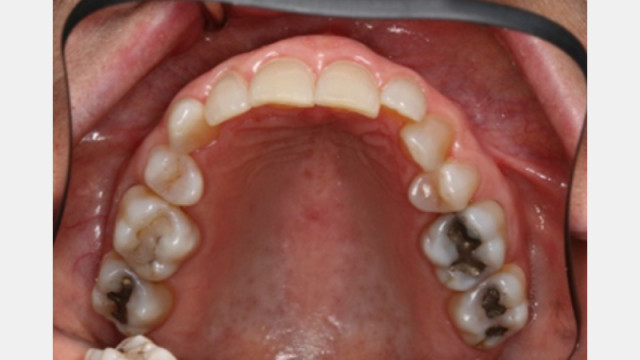

Customized Impression Coping for a Single Tooth Implant in a Maxillary Central Incisor

Follow this visual essay for steps to fabricate a personalized impression coping to optimize the transfer of the peri-implant soft tissue architecture to the laboratory.